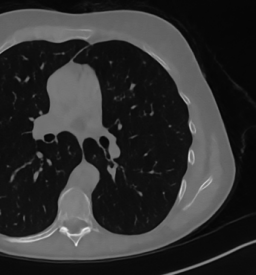

We now consider the CT protocol whose results are reported in Figure 6.

In this case, the tomographic reconstruction is more challenging than in the previous experiment. The starting image has evident streaking artifacts and blur and some details are lost, especially in the first zoom. The artifacts are reduced in the (top right image), where some details are recovered and the edges are quite neat.

The image obtained with the proposed RISING (bottom right) is visually an excellent reconstruction. It is very similar to the image, whose training, we remark, is based on more informative target images.

In Figure 7 we plot for these experiments, the same profiles of Figure 5.

In the left graph, we analyse the performance of LPP approach: the reconstruction gets values quite close to the GT, but it does not fit well the target black line.

In the right graph, we analyse the performance of RISING approach: the solution almost overlaps the target profile, confirming that the network has correctly learned.